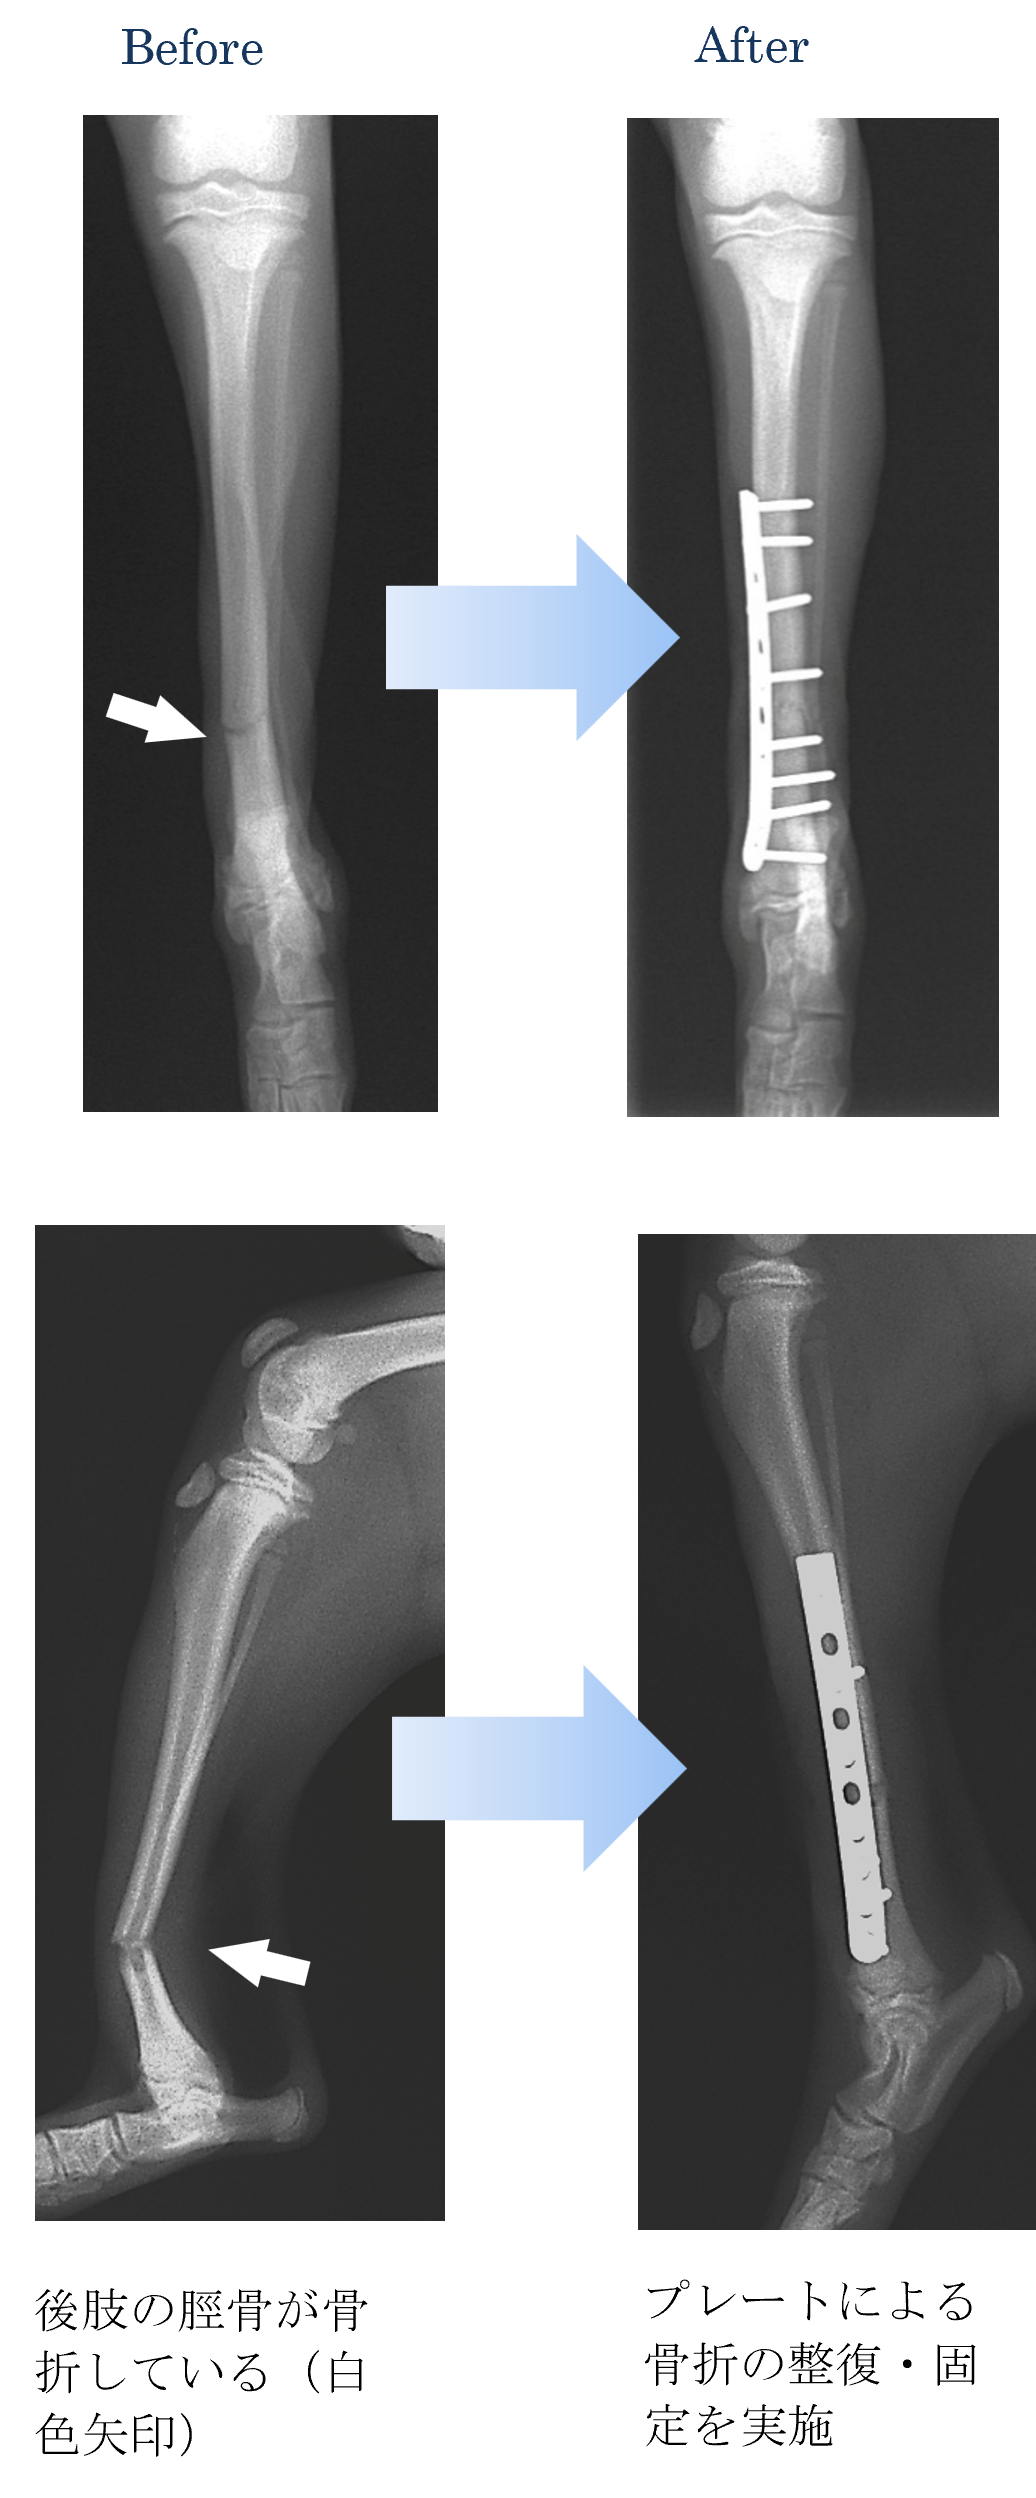

後肢をドアに挟んでしまい、肢を挙上して痛がっている。

各種検査より、脛骨(すねの骨)の骨折と診断しました。

ご家族と相談した結果、手術による骨折の整復および固定を実施することになりました。

手術して次の日には、後肢を地面に着くようになりご家族の方も大満足でした。